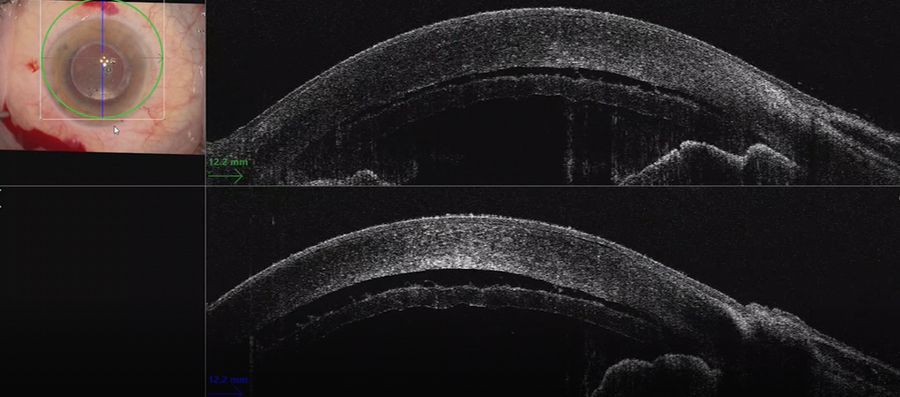

In this case, a Descemet rhexis was created. The clear red reflex on the Proveo 8 with EnFocus intraoperative OCT allowed clear visualization of Descemet’s membrane peeling and endothelium.

When performing DSEK in eyes that have had a penetrating keratoplasty or other pathologies such as posterior membrane dystrophies, it is valuable to see DM as opposed to stromal tears or folds.

When performing the strip, the intraoperative OCT provided live confirmation of where DM was present. This is particularly helpful when there is a poor view e.g. in this case of ocular trauma. The OCT showed the separation of Descemet’s membrane very clearly.